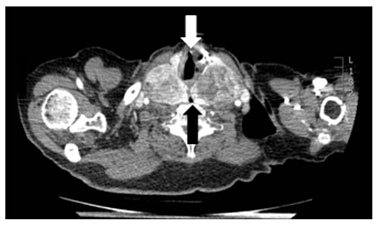

Laboratory testing reveals a TSH 1.14μU/mL (0,35-5,28). Chest radiography does not show tracheal deviation. Gastroscopy does not present esophageal alterations. Cervicothoracic CT shows a multinodular goiter with posteromedial spreading of both lobes that compress faryngoesophageal union and proximal esophagus (black arrows in Figures 1 and Figure 2). Also, larynx and trachea are displaced forward (white arrows in Figures 1 and Figure 3). Right thyroid lobe measures 5,2x4,9x7,8cm. Left thyroid lobe measures 5,7x4,9x8,8cm. Patient is dismissed for surgery due to high anesthetic risk. Currently, patient tolerates turmix diet and fluids with thickeners. Although isolated dysphagia is an uncommon symptom in compressive goiters, whose main manifestation is dyspnea, it is important to rule out an enlargement of the thyroid gland as a cause of dysphagia even in the absence of dyspnea, dysphonia or visible goiter.

Figure 1